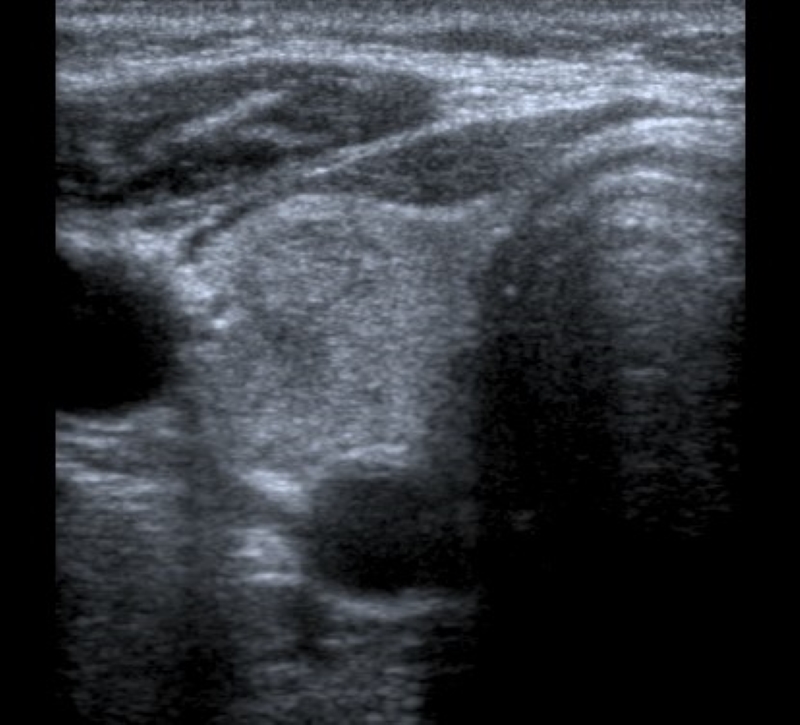

Márgenes

Es el borde entre el nódulo y el parénquima tiroideo adyacente o las estructuras extratiroideas. Se clasifican en “lisos” (Fig. 4) cuando son bien definidos, curvilíneos, de forma esférica o elíptica y no presentan interrupción en su extensión; “irregulares” (Fig. 5) cuando son espiculados o dentados, y puede dibujarse todo el contorno, lo que los diferencia de los “mal definidos” (Fig. 6), en los cuales es difícil distinguir adecuadamente del parénquima tiroideo. Se denominan “lobulados” (Fig. 7) cuando presentan protrusiones redondeadas y de diferentes tamaños. El “halo” (Fig. 8) es un anillo hipoecoico que rodea al nódulo, y puede rodearlo en forma parcial o completa. Este se considera una cápsula fibrosa que se observa más comúnmente en nódulos benignos, aunque también puede estar presente en algunos nódulos malignos2,18. En la literatura publicada, la mayoría de los autores mencionan que el tipo de márgenes que más frecuentemente se asocia a malignidad son los irregulares1,2,12,15,19,20,21,22, mientras que otros autores indican a los mal definidos16,23) como característica de malignidad.